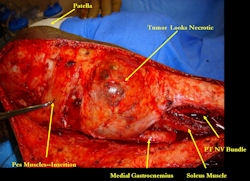

Examples of radical limb sparing surgeries for osteosarcomas in various anatomic locations (distal femur, proximal tibia, proximal humerus, scapula)

In each case, the tumor and bone from which it arose were resected. This required meticulous dissection, mobilization and preservation of adjacent pertinent neurovascular structures. In each case presented here, the defect was reconstructed with a special modular segmental tumor prosthesis. This also replaces the adjacent joint in many instances.

Limb-sparing surgery for osteosarcoma of distal femur – Intraoperative photos

Intraoperative photos